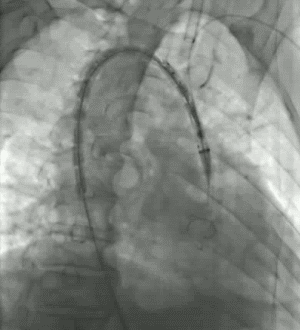

★ 病例1:主动脉弓夹层大裂口

★ 病例2:主动脉弓动脉瘤III型弓

III型弓,血管扭曲,LSA与主动脉呈锐角

术后造影无内漏,各分支形态良好,血流通畅